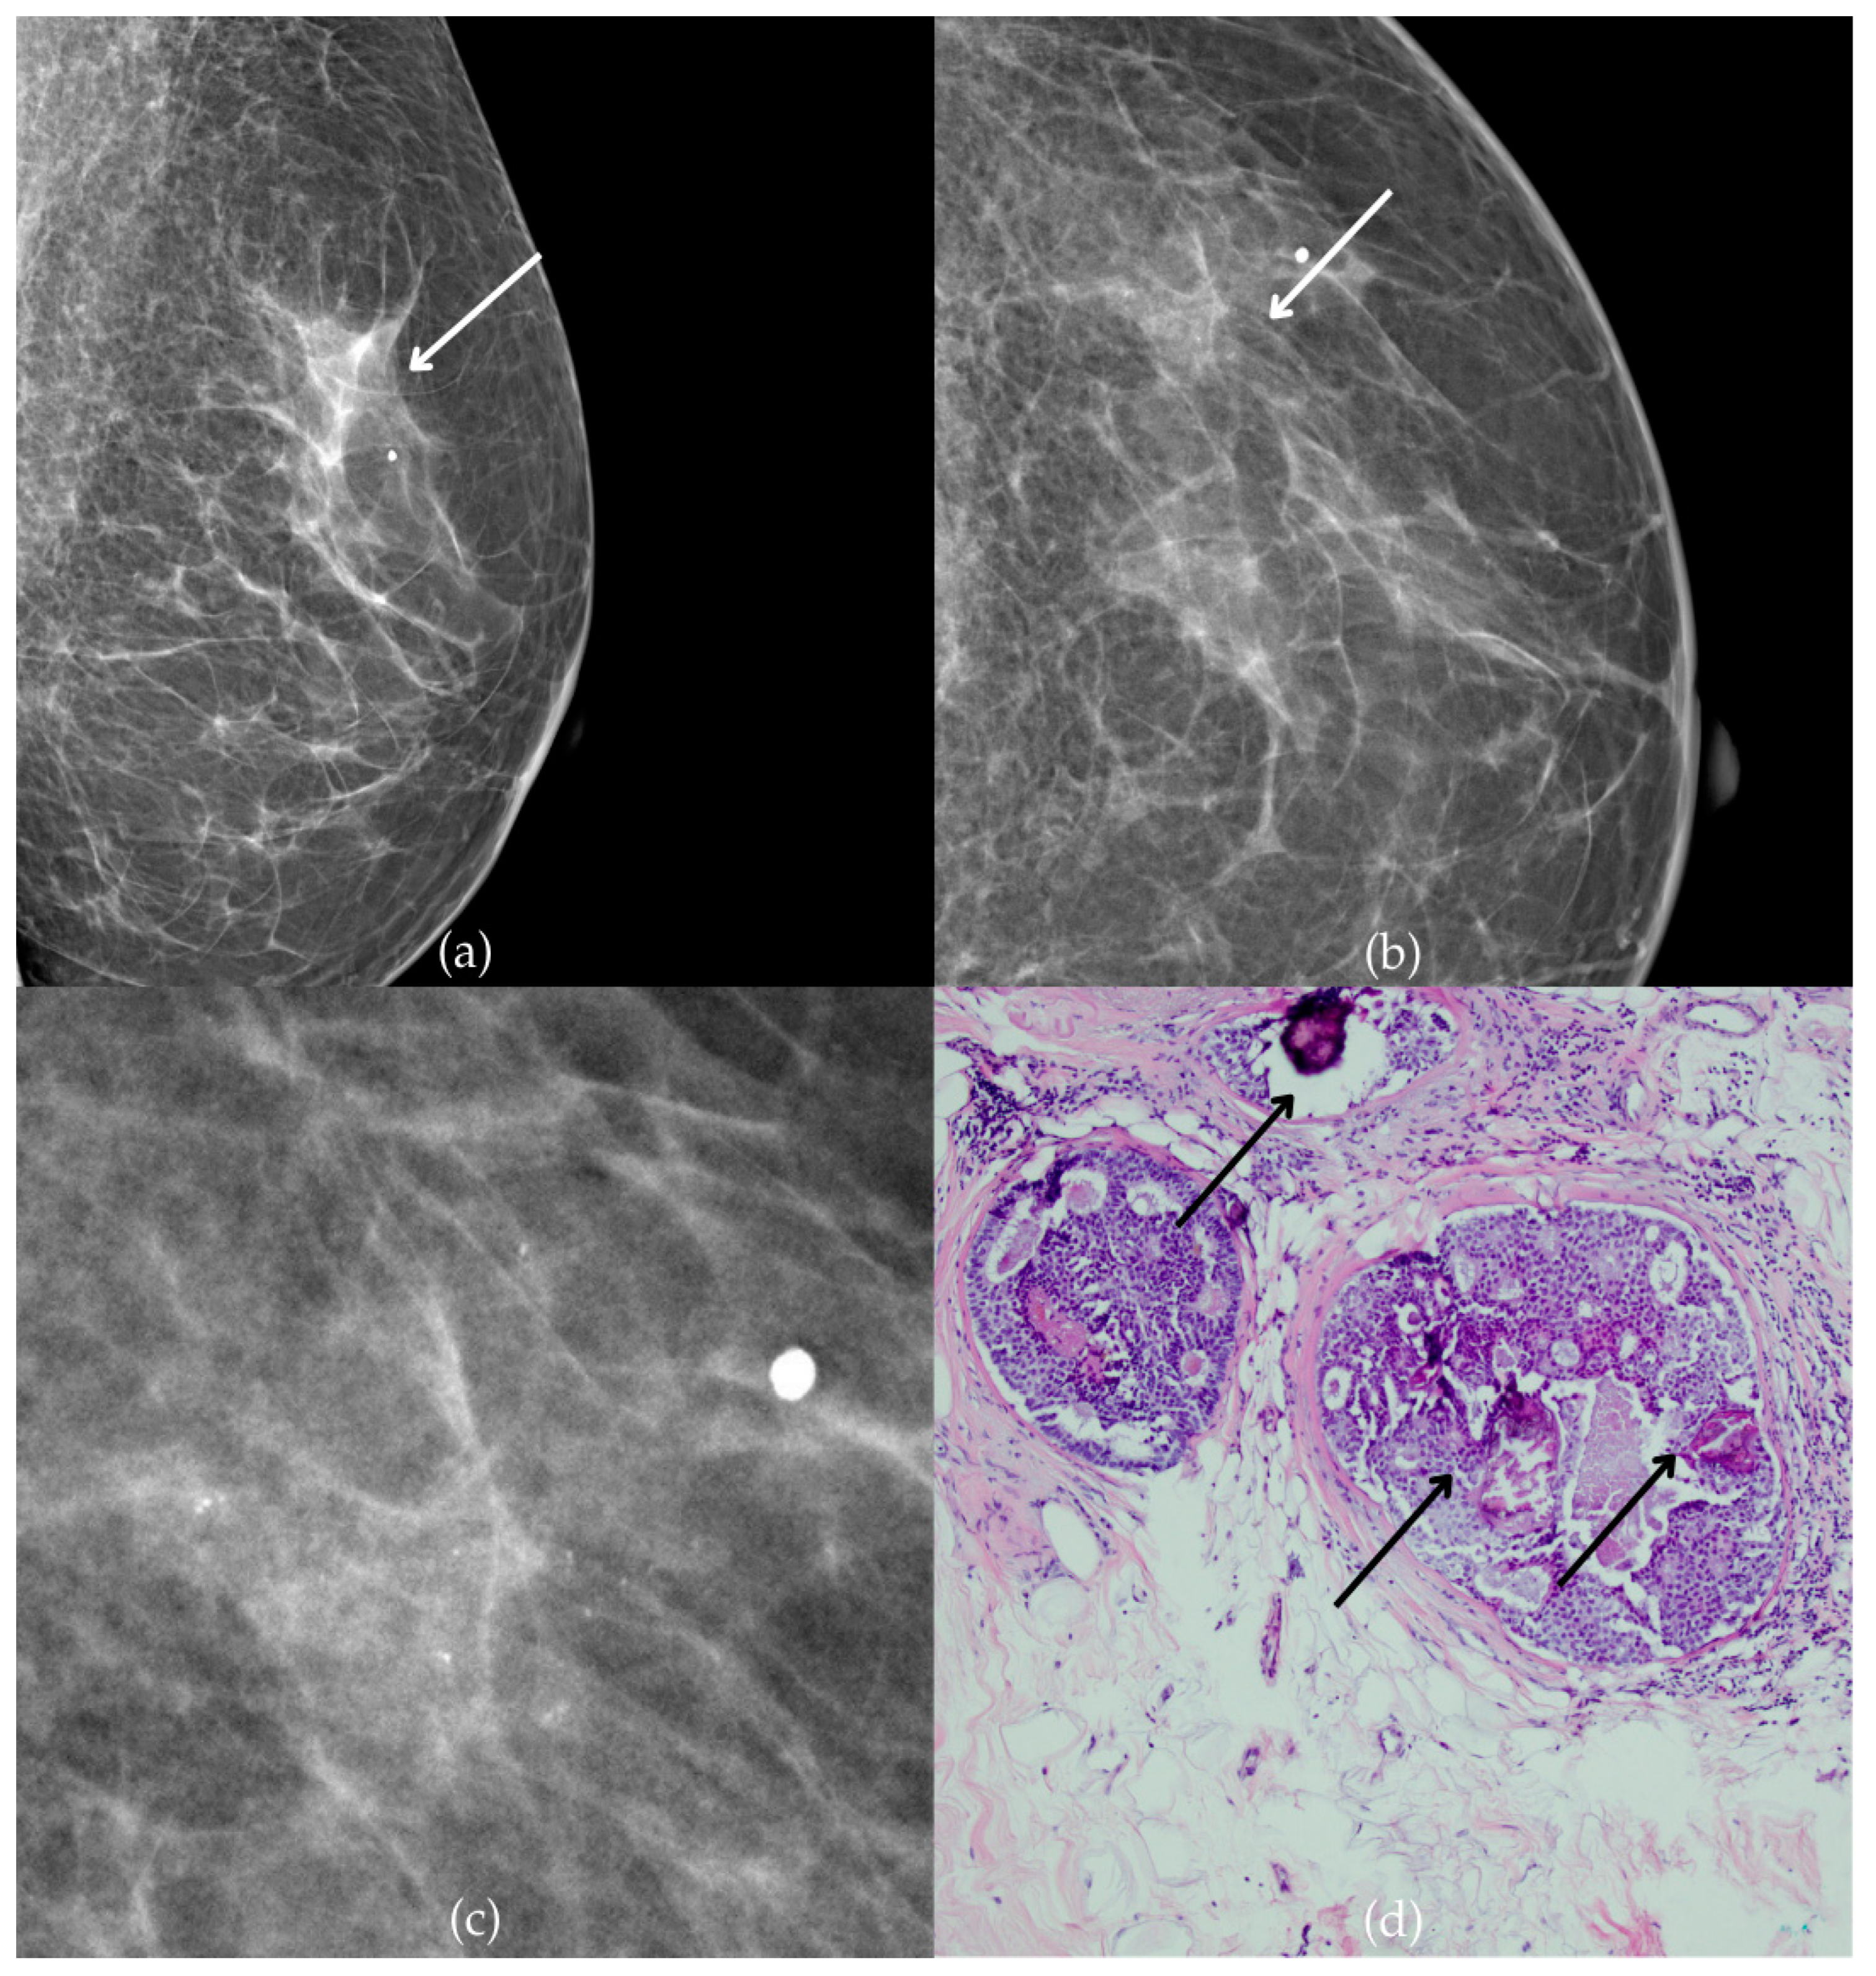

During a screening program, a 64-year-old patient presented with suspicious microcalcifications. The mammogram shown in Figure 3 of the patient’s right breast revealed a segmental distribution of coarse heterogeneous and fine pleomorphic calcifications in the upper outer quadrant, corresponding to a BI-RADS 4 finding. Tissue analysis obtained through VABB confirmed the presence of invasive carcinoma (category B5b). The patient underwent a mastectomy. Postoperative pathology showed only an in situ component, with no evidence of an invasive component, indicating that the invasive component was removed during the biopsy. One year after diagnosis, the follow-up US was reported as BI-RADS 2 classification, indicating benign imaging features.

Invasive breast cancer. (a) Mediolateral oblique (MLO) mammography view; (b) craniocaudal (CC) mammography view of the right breast showing coarse heterogeneous and fine pleomorphic calcifications (marked with arrows) in the upper outer quadrant, with segmental distribution. (c) Magnified mammographic image of coarse heterogeneous and fine pleomorphic calcifications with segmental distribution. (d) The histopathological image of the biopsy sample shows the characteristic features of invasive cancer (marked with arrow) and ductal carcinoma in situ (DCIS) (marked with arrowhead) (HE staining; 40× magnification).